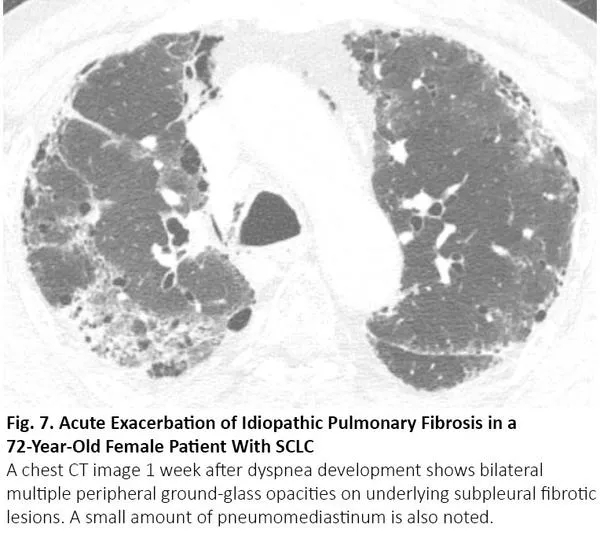

吸烟增加罹患肺癌和特发性肺纤维化(IPF)的风险,特发性肺纤维化患者罹患肺癌的风险会增加。当患者接受手术或放疗时,若特发性肺纤维化急性加重,CT可呈现双肺弥漫性或外周磨玻璃影,17与COVID-19肺炎相同(图7)。

图7. 一位72岁的小细胞肺癌女性患者出现特发性肺纤维化急性加重